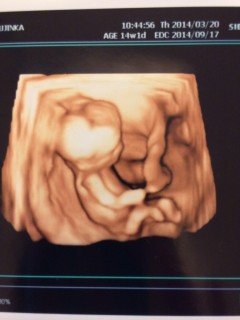

初めての3Dエコー(≧∀≦)

元気に動き回っていて安心しました。

CRL81.8mm

もう赤ちゃんの形をしているのでびっくり!!後ろ姿が何とも言えないかわいさ。

心臓が4つのお部屋に分かれているのが確認出来ました。耳がパパ似?!